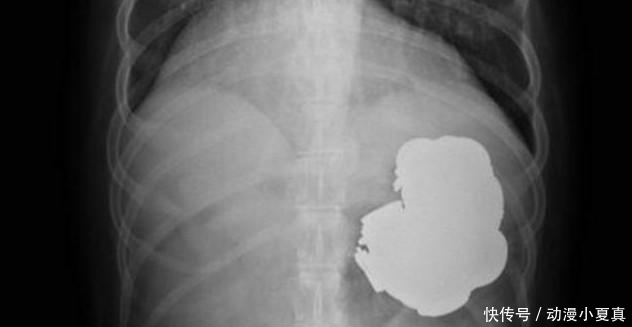

但是在医生的简单的处理下,该男子的情况没有好转而更加疼痛,家人十分焦急。医生很诧异,研究后决定给男子做X检查以及胃镜检查,检查后的结果让在场所有的医护人员感到吃惊,男子胃里的东西让临床多年的医生感到害怕。

男子胃里到底是什么呢?最有医生给出了结果。男子的胃里居然是金属物品,并且里边的金属物品还杂乱无章,粗略的估算下,有一百多枚钱币、几十根银还有些许螺丝、螺栓,让医生感到吃惊的还有废弃电池。医生非常诧异,难道男子把自己当成了机器人?医生把检查的结果告知了男子家人,并且医生告诉男子家人,必须要马上做手术,要不然该男子会因此而丧命。